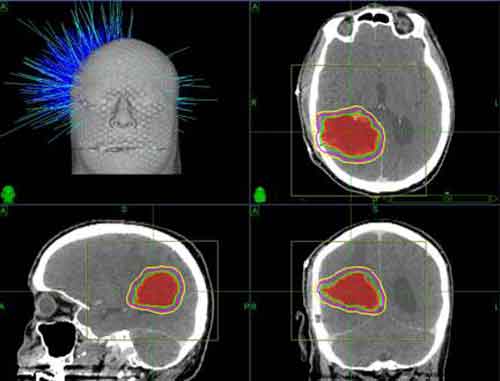

Tra 300 e 400 pazienti con metastasi cerebrali sono curati ogni anno presso la MedUni di Vienna. La cura standard nella maggior parte dei casi è la radioterapia alla testa o l’irradiazione generalizzata al cervello, che comportano dei rischi e possibili effetti collaterali. Solo in qualche caso sono disponibili metodi a base di farmaci per certi tipi di cancro. Preusser mette in risalto il potenziale delle scoperte, “Le nostre scoperte potrebbero rappresentare un importante passo verso lo sviluppo di forme di cura meno aggressive,” dice.